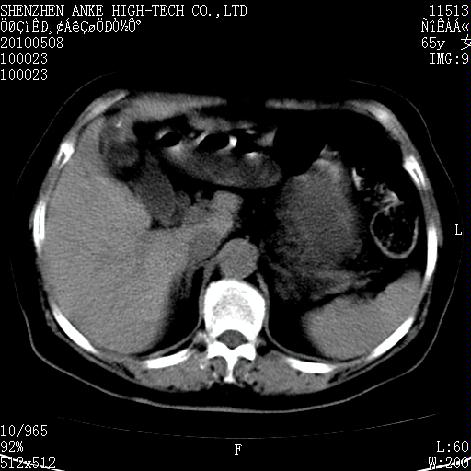

女,65岁。乳腺ca术后多年。现在剧烈腹痛待查。b超示胆囊炎、胆结石。

左侧乳腺癌术后,胸骨柄见有骨质破坏,考虑乳腺癌骨转移,胆囊炎,右肾囊肿。

1)胆囊炎。2)右肾囊肿。3)左侧少量胸腔积液。4)建议行ect检查排除胸骨转移瘤。

1)胆囊结石、胆囊炎。2)右肾囊肿占位。3)左侧少量胸腔积液。4)建议行ect检查排除胸骨转移瘤。

5)调整窗宽、窗位注意观察腹腔内有否游离气体(能看清腹内脂肪及气体)。